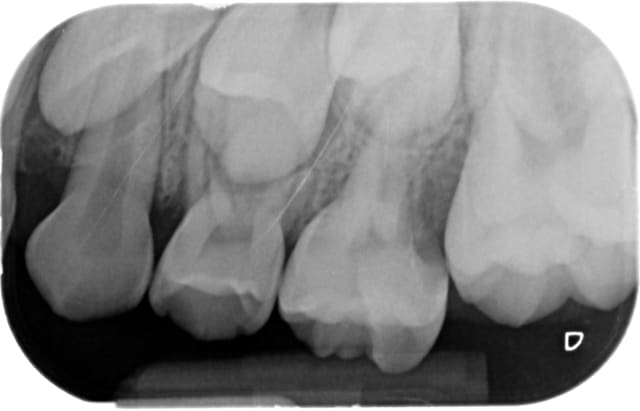

J'aimerais bien une rétro de 26-27 y'a un souci non ?

ya comme une atteinte de la furcation.

La 27 semble refoulée en distal par un obstacle, et sur la racine distale de la 26 il y a un halo radioclaire...